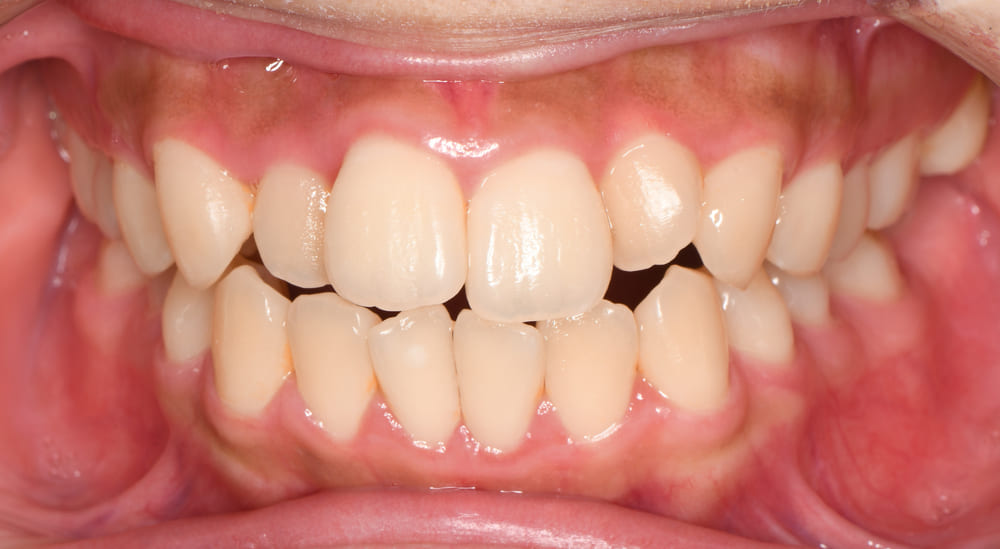

次に正面の口腔内写真をご紹介します。

いわゆる八重歯(犬歯の低位唇側転位)が認められ、側切歯と言われる前から2番目の歯も不正な位置に萌出しています。